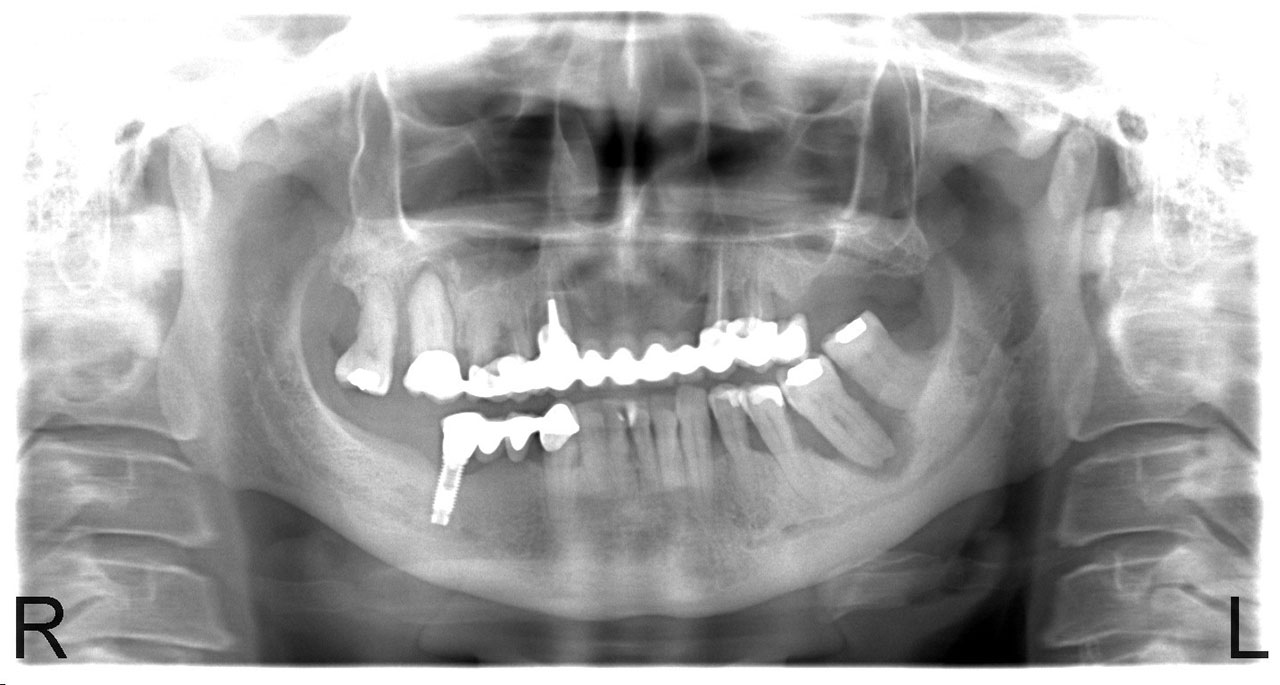

Sikerét mindenekelőtt a gyorsaságának köszönheti, hiszen a mai rohanó világban kinek van ideje, kedve fogatlanul otthon ülni heteket, hónapokat a fogpótlásra várva? Az Ihde implantációs eljárás során a páciens azonnal, de legkésőbb 72 óra múlva egy rögzített (tehát nem mozgó, nem kivehető) pótlással hagyja el a rendelőt. Ez az egyedülállóan gyors eljárás annak köszönhető, hogy azonnal tudunk implantálni szinte bárhova, akár foghúzás után is, továbbá a művelet nem jár nagy feltárásokkal, nincs szükség csontbeültetésre, így a gyógyulás folyamata is nagyon gyors és a beültetés technikájának köszönhetően maximum 72 óra múlva a korona is feltehető. Tehát ennyi idő alatt foga lesz a betegnek és az implantátum azonnal terhelhetővé is válik.

Az eljárás mellett szól az is, hogy nagyon biztonságos. A cég adatai alapján a beültetett implantátumok 98.2%-a sikeres. Az azonnali terhelésű implantátumokkal rögtön, akár foghúzás után is szinte bárhová lehet implantálni, bárkinek, legyen szó cukorbeteg, dohányos, vagy akár csontritkulásban szenvedő páciensről. Ennek köszönhető, hogy a betegek 99%-ánál alkalmazható a módszer.

Természetesen, az Ihde Azonnal Terhelhető Implantátum Rendszer alkalmazása speciális szaktudást igényel, így elengedhetetlen az orvosok gondos és folyamatos képzése. Ez, illetve a kiváló minőségű svájci alapanyagok és a sok évtizedes, precíz, innovatív gyártási technológia együttese adja, hogy a cég kiemelkedően magas (98,2%-os) sikert ér el, az Ihde implantátumok bent maradásának mérésekor.